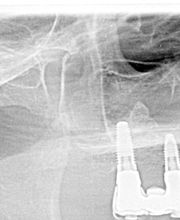

Das Bodensee Implantat Zentrum (ZIP) ist Ihre führende Praxis für Zahnheilkunde in der Region. Wir sind spezialisiert auf hochwertige Implantologie, einschliesslich des All-on-4® Konzepts, für das wir als Excellence Center Gold-zertifiziert sind. Unser Leistungsspektrum umfasst Komplettsanierungen, Kronen, Brücken sowie ästhetische Behandlungen. Mit über 30 Jahren Erfahrung bieten wir auch Angstpatienten eine einfühlsame Betreuung und Behandlungen unter Narkose für ein strahlendes Lächeln.